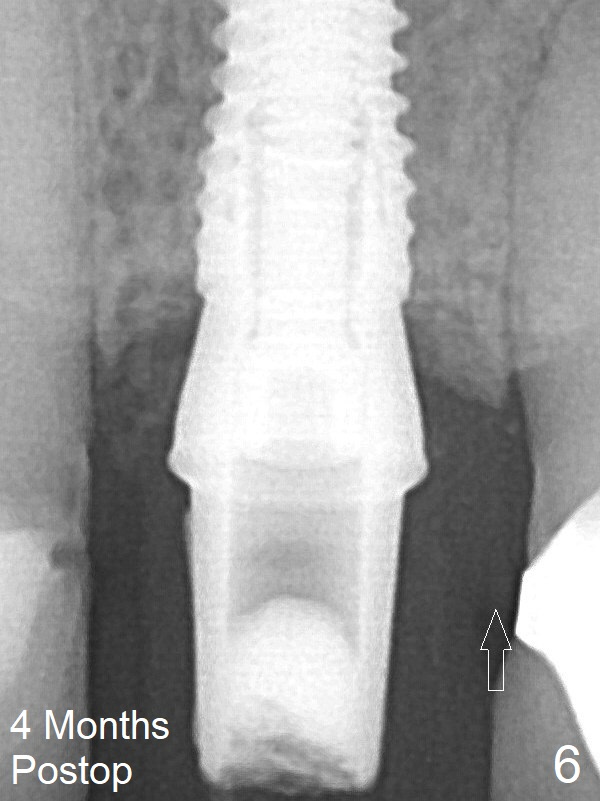

She returns for impression 4 months postop; the abutment margin is substantially subgingival (Fig.6 arrow). The abutment is changed to 4.5x4(4) mm one before impression. There is no bone resorption 9 months post cementation (14 months postop, Fig.7).